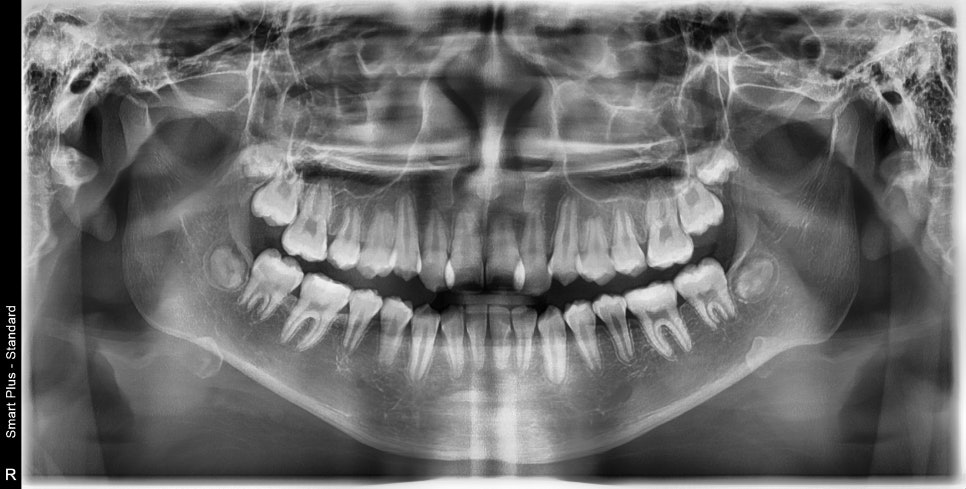

두번째 치아가 덧니로 있는 경우의 치료는 흔한 경우지만

생각보다 많은 노하우가 필요한 치료라고 생각합니다.

최후방 치아 맹출에 따른 치료기간 연장

교정 치료 중에 화살표 최후방 치아가 맹출하여,

이 치아를 배열하는 과정에서 치료가 조금 더 길어지긴 했습니다

최후방 치아가 나올때 약간 삐뚤게 나옴으로 인해 1회 재제작을 했습니다.